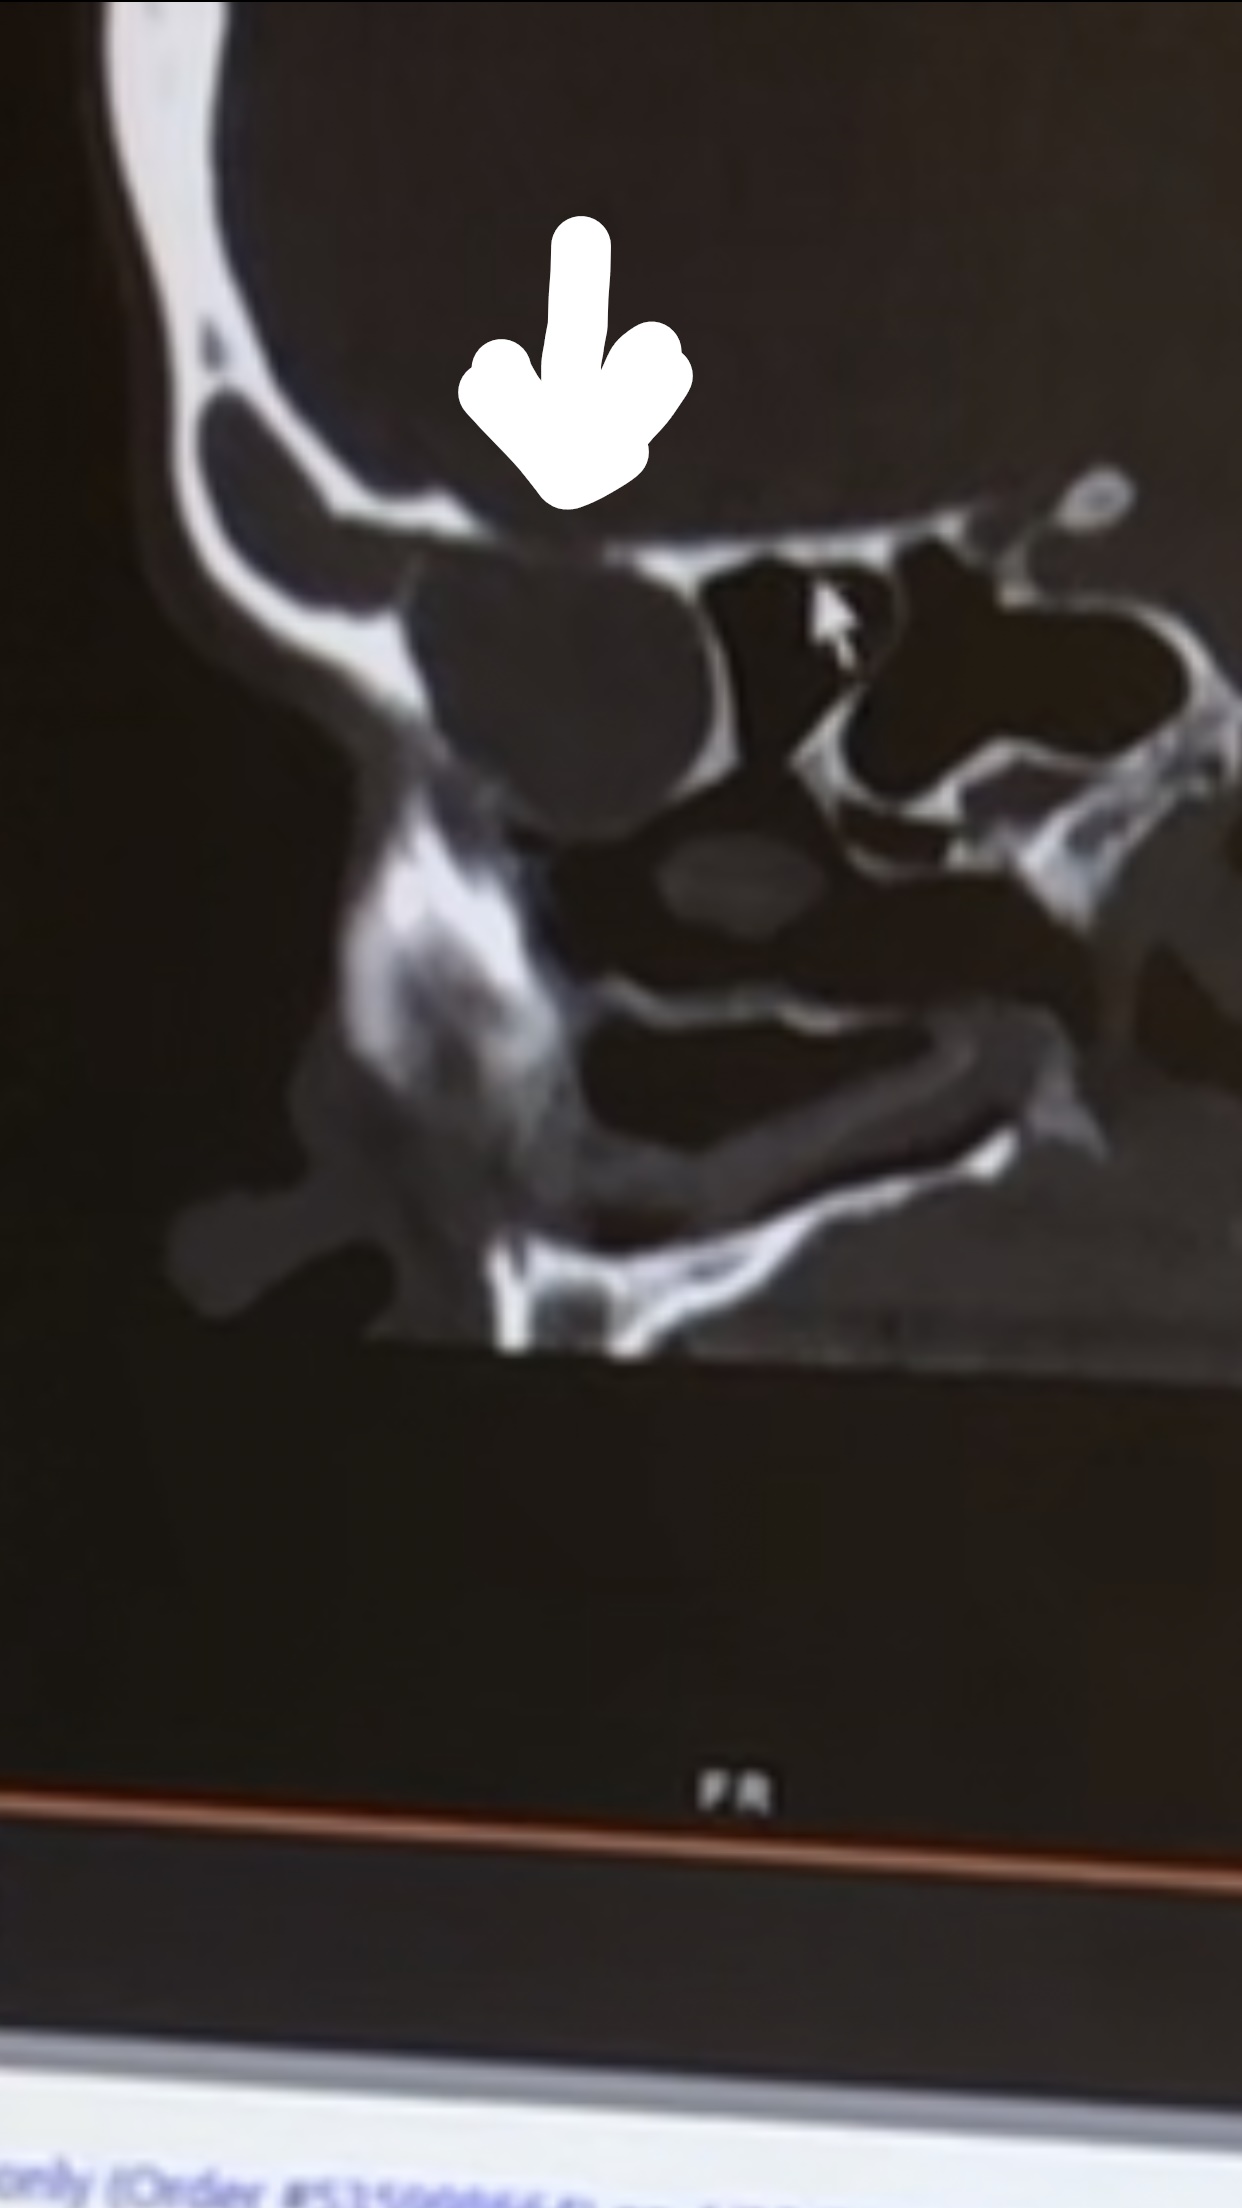

So fast forward to my appointment. I was seeing the head surgeon of Otolaryngology (a head and neck surgeon) at Duke. I saw another Doctor first, I think he was doing his rotation in that area of study, and he as you can imagine asked me a zillion questions as they do at teaching hospitals. I am used to it as I usually go to Duke for my medical needs as I am “high risk” whatever that means. It was not until the Doctor started asking me the same questions, have you had headaches, eye pain, and so on that, I started telling him about what I thought were weird experiences I had that had come to mind over the week between Dr. O’Neil’s questions and this appointment. I recalled several times having what I remembered once telling Chip that I thought I was having a stroke or at the very least Bell’s Palsy. I was out of town at a meeting, and I was at the hotel talking with a co-worker when my left eye began hurting really bad and I began to feel like the left side of my face was drawing up. It was so bad that I wondered if the person I was talking to could see it. I excused myself and when I went to the room I went straight to the mirror. The left side of my face felt like it was pulling on the inside, and my eye was hurting, but it looked fine in the mirror. I honestly thought I was going to have a stroke that night. The next morning this was fine, but it happened a couple more times over the next couple of years. I always tried to figure it out as every time I was talking to someone at an odd angle, and I thought it had something to do with holding my eye in a turned position too long. I always tried to find a logical explanation for things that did not seem right, but I never follow-up on them, and live with it. I have had headaches for so long that I did not even think about them, they were part of my life, and I continuously took over-the-counter pain medication only when it was too bad to tolerate. So, when Dr. O’Neill asked about headaches, I did not think much about it, but over the next week of course I did think about it as well as focused on the headaches, where was it hurting, did it seem any worse, and I shared this information with the doctor. I had complained to my family for months that my face hurt like it felt swollen. I was constantly taking my glasses off because they were pushing against my face, though I am blind as a bat without them and could not leave them off for long. Little things that I had not thought much of were now jumping out at me like I had complained of facial pressure when I bent over. I always thought I had the weirdest issues and would keep pushing on. So, apparently, everything I described to him was what was expected with tumors like this. Wait, what? A tumor? I thought I had an infection. The head surgeon, who is beyond amazing and not bad to look at either, though I am old enough to be his mother I am sure, showed me the CT scan, and apparently, these things had deteriorated the bone of my left eye orbit and at the base of my brain on the left as well.

The large arrow is pointing to the mass that had deteriorated my skull.